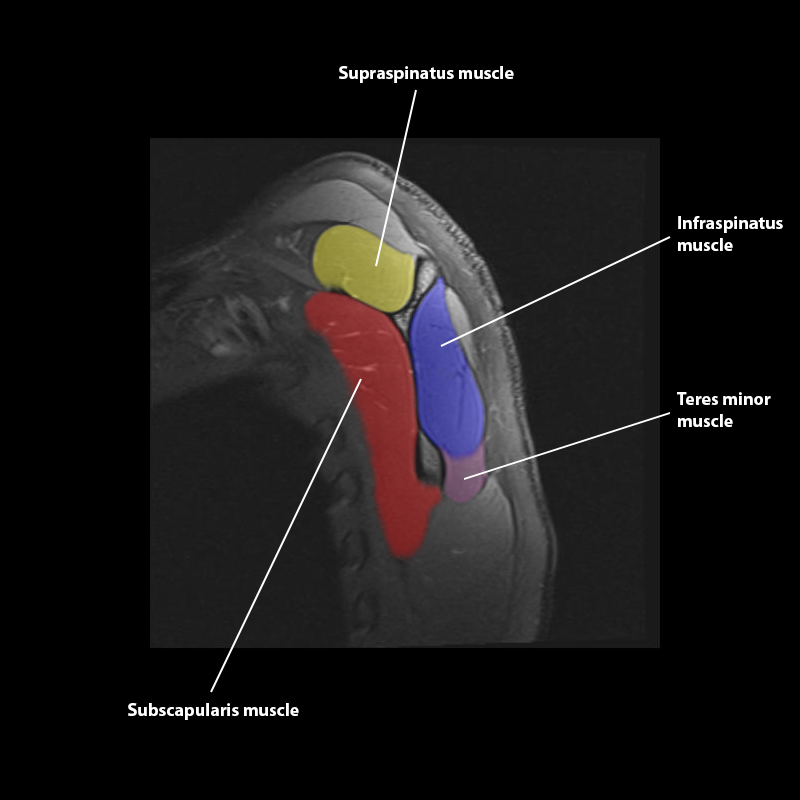

Shoulder MRI Anatomy